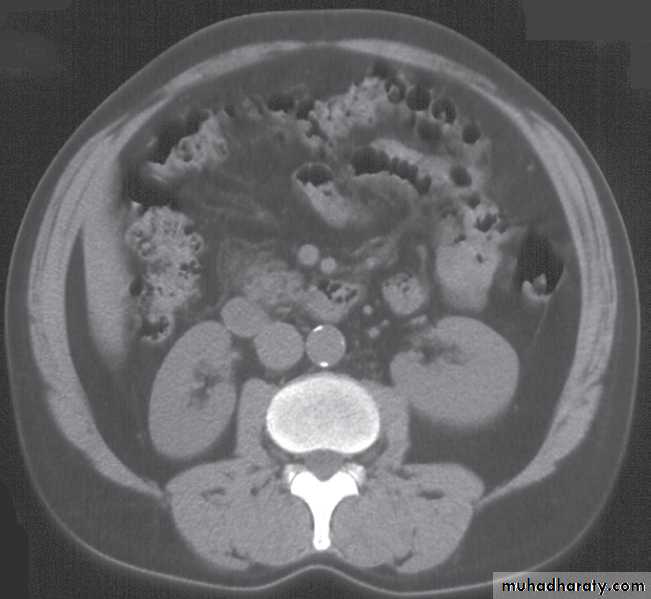

Computed tomography urography

CT is initially performed without intravnous contrast medium (non-contrast CT or ‘CT KUB’) to identify calcification .indication and include:

(i) The early renal cortical enhancement phase.(ii) The homogeneous nephrogramphase; and

(iii)The delayed urographic phase, obtained

several minutes later to demonstrate

contrast within the collecting systems.